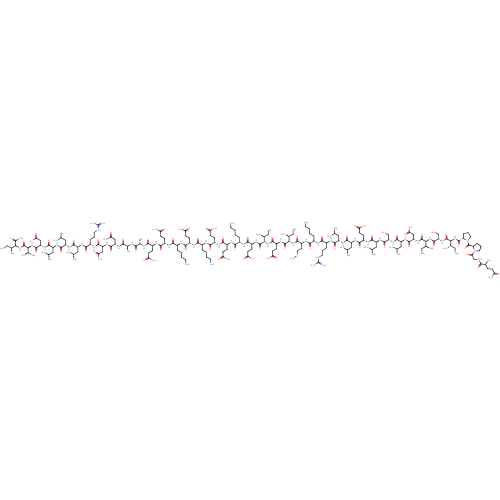

TargetCorticotropin-releasing factor receptor 1(Homo sapiens (Human))

Dupont Pharmaceuticals

Curated by ChEMBL

Dupont Pharmaceuticals

Curated by ChEMBL

Affinity DataEC50: 0.220nMAssay Description:Activity of peptidic agonists on corticotropin releasing factor receptor receptor using agonist-stimulated adenylate cyclase assayMore data for this Ligand-Target Pair